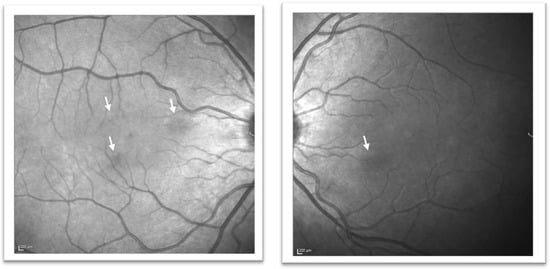

Figure 3.

Near-infrared reflectance images in December 2020. The lesions seen on near-infrared reflectance imaging from initial presentation are seen to have become much less prominent over the 10-month period (white arrows).

Despite being overlooked at the time, the near-infrared reflectance image from February 2020 did, in fact, demonstrate three discrete perifoveal hyporeflective lesions in the right eye and one in the left (Figure 1A), with SD-OCT scans demonstrating hyperreflective bands in the outer nuclear (ONL) and outer plexiform layer (OPL) and additional loss of clarity of the outer retinal bands (Figure 1B). These lesions corresponded to the lesions seen on clinical examination in December, and to the negative scotomata the patient had been reporting. The lesions highlighted on near-infrared reflectance had become significantly less prominent over the preceding 10 months (Figure 3). Based on the clinical findings, and in keeping with the history and patient demographics, a diagnosis of acute macular neuroretinopathy was made. The patient was reviewed again in March 2021, at which time symptoms persisted but were less prominent. The lesions seen on near-infrared reflectance were continuing to resolve, but ONL/OPL hyperreflectivity persisted on SD-OCT although this was progressively less prominent on the December 2020 and March 2021 scans, with some improvement also seen in the outer retinal band configuration (Figure 1B).